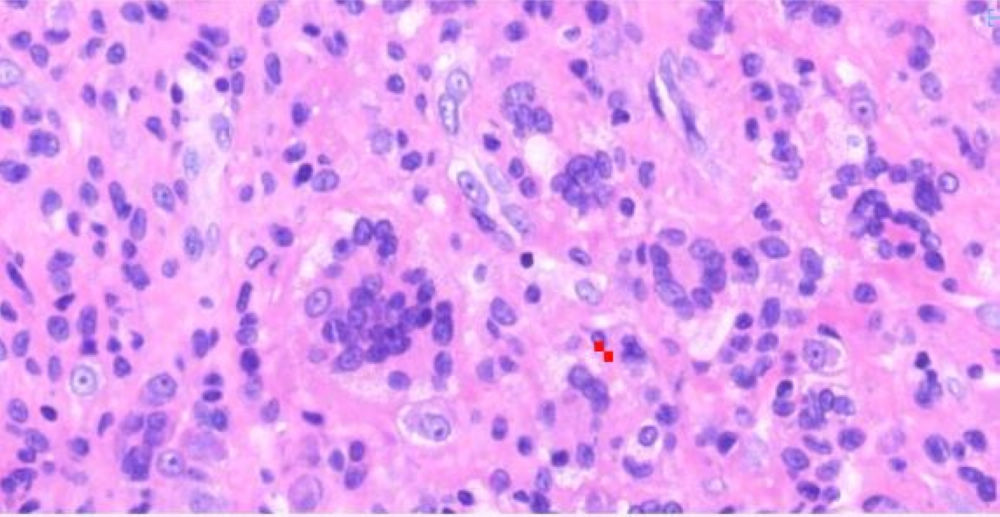

小土豆跟着农人老师学本领-食道手术切除 粘膜表面鳞状上皮缺乏异型性 基底部细胞排列紊乱 浸润性生长  鳞癌